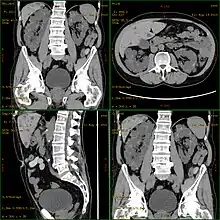

![]() | |

Severely affected polycystic kidneys removed at time of transplantation | |